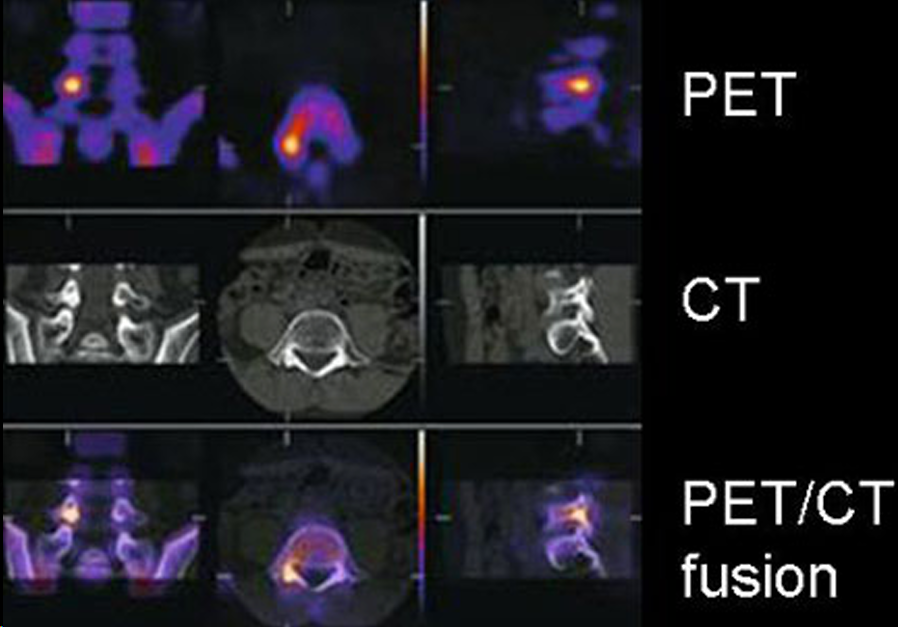

**PET TC o Tomografía por Emisión de Positrones – Tomografía Computarizada

- PET: Tomografia por emision de positrones

- Se inyecta un radionúclido generador de positrones 18F

- Se necesita un ciclotrón cercano

- El 18F se une a la glucosa 18FDG (trazador)

- Valoramos la via glicolítica de la glucosa Las células tumorales tienen un metabolismo muy incrementado Captan la glucosa marcada

- Unidades SUV (standard uptake value). Si son > 2.5 ó 3 = NEOPLASIA

Hay diferentes tipos de PET y crean imagenes de fusion danto tanto imagen anatomica como funcional al mezclarla IMPORTANTE